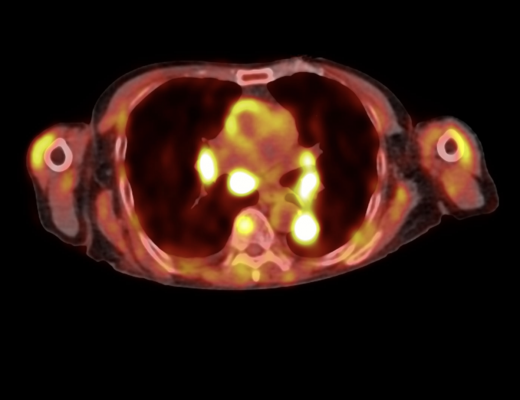

The RefleXion X1 machine with BgRT is designed to overcome the technical limitations that currently restrict radiotherapy to one or two tumors. When available, RefleXion will scale BgRT to treat all visible tumors, even those that move rapidly due to bodily functions such as breathing or digestion, in the same treatment session.

RefleXion recently announced FDA clearance for stereotactic body radiotherapy (SBRT), stereotactic radiosurgery (SRS) and intensity modulated radiotherapy (IMRT), and its first clinical and commercial client.